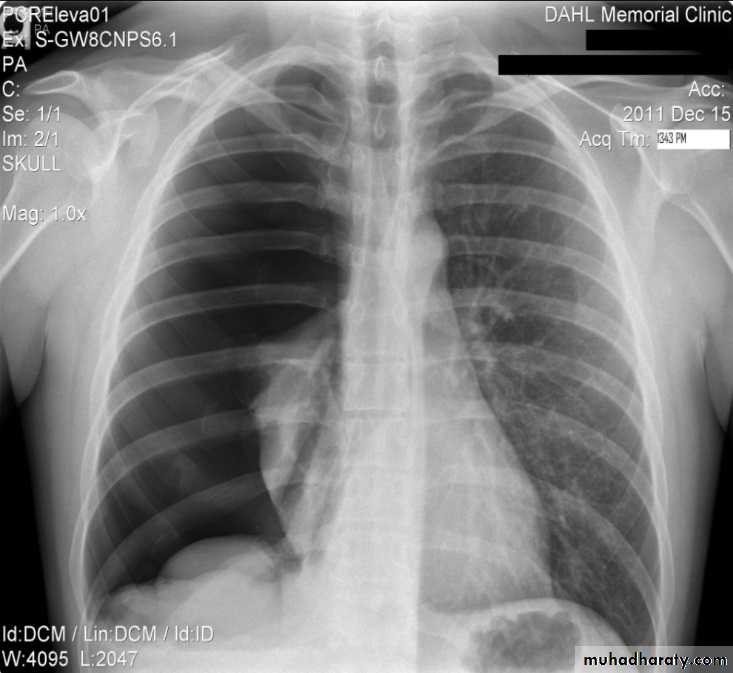

Hydro pnuemothorax

Hydropneumothorax is a term given to the concurrent presence of a pneumothorax as well as a hydrothorax (i.e. air and fluid) in the pleural space.Plain radiographs

On an erect chest radiograph, recognition of hydropneumothorax can be rather easy - and is clasically shown as an air-fluid level. On the supine radiograph, this may be more challenging where a sharp pleural line is bordered by increased opacity lateral to it within the pleural space may sometimes suggest towards the diagnosis